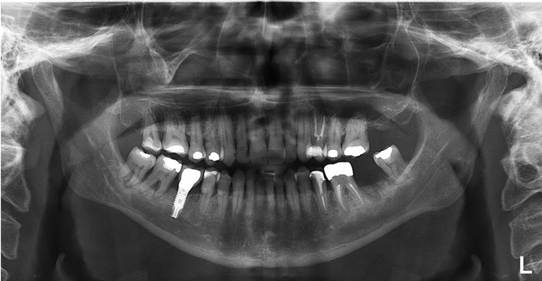

Paciente L. S. S, gênero masculino, 76 anos de idade, compareceu ao consultório particular para avaliação clínica. Durante a anamnese, paciente informou que realiza acompanhamento cardiológico e endocrinológico em virtude da hipertensão arterial e diabetes mellitus. Ao exame clínico e radiográfico (Figura 08), ausência do 26, e pouco suporte ósseo, com mobilidade excessiva, no elemento 27.

Figura 08. Radiografia panorâmica inicial

Figura 09. A, B) Radiografia periapical final. C) Radiografia panorâmica final.